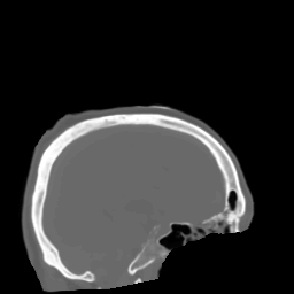

Model-based treatment planning for transcranial ultrasound therapy typically involves mapping the acoustic properties of the skull from an x-ray computed tomography (CT) image of the head. Here, three methods for generating pseudo-CT images from magnetic resonance (MR) images were compared as an alternative to CT. A convolutional neural network (U-Net) was trained on paired MR-CT images to generate pseudo-CT images from either T1-weighted or zero-echo time (ZTE) MR images (denoted tCT and zCT, respectively). A direct mapping from ZTE to pseudo-CT was also implemented (denoted cCT). When comparing the pseudo-CT and ground truth CT images for the test set, the mean absolute error was 133, 83, and 145 Hounsfield units (HU) across the whole head, and 398, 222, and 336 HU within the skull for the tCT, zCT, and cCT images, respectively. Ultrasound simulations were also performed using the generated pseudo-CT images and compared to simulations based on CT. An annular array transducer was used targeting the visual or motor cortex. The mean differences in the simulated focal pressure, focal position, and focal volume were 9.9%, 1.5 mm, and 15.1% for simulations based on the tCT images, 5.7%, 0.6 mm, and 5.7% for the zCT, and 6.7%, 0.9 mm, and 12.1% for the cCT. The improved results for images mapped from ZTE highlight the advantage of using imaging sequences which improve contrast of the skull bone. Overall, these results demonstrate that acoustic simulations based on MR images can give comparable accuracy to those based on CT.